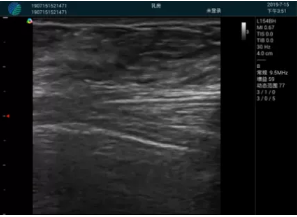

頸動脈血流充盈飽滿,無外溢

肝內(nèi)血管顯示清晰,血流敏感無外溢